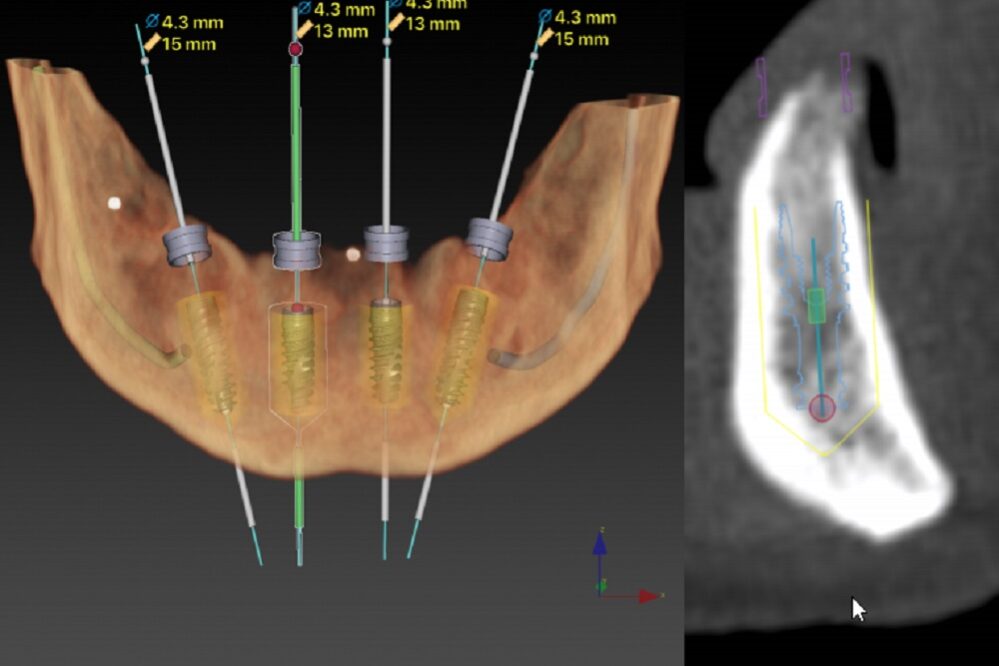

All-on-four therapy concept of the edentulous jaw consists of placing four dental implants and replacing twelve teeth in one jaw. Due to progressive bone loss in lateral regions of the lower and upper jaw or increase (pneumatisation) of maxillary sinus in the upper jaw and proximity of the mandibular nerve in the lower one, we often need big bone augmentations, so that we can ensure adequate bone volume for the integration of implants.

All-on-four therapy treatment enables rehabilitation of all lost teeth without the necessary bone augmentations. What is it about? There is often enough bone volume in the anterior part of the jaw to place the implants. By modifying the technique of an implant bed preparation, lateral implants are placed with inclination, so that the load field is increased, and consequently, we can replace a series of twelve teeth with the placement of only four dental implants.